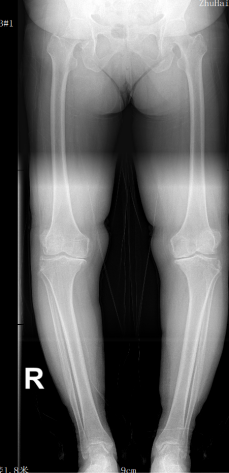

患者王阿姨,在海外生活多年,深受膝关节疼痛之苦,多年来四处求医问药。尽管在国外尝试了多种药物治疗和物理治疗手段,但疼痛依旧未能得到有效缓解。医生建议进行膝关节置换手术,然而国外高昂的手术费用和漫长的预约等待时间,让王阿姨望而却步。一下飞机,就立即赶往pilipili 寻全华山主任诊治,经过全主任的详细检查和评估,确诊为严重的膝关节骨关节炎,需进行膝关节置换手术。

术后 术前

术后,医护团队立即展开了精细的护理,并制定了康复方案。为了帮助患者早日恢复,医护人员逐步引导王阿姨进行关节功能锻炼,同时密切关注术后的疼痛管理和感染预防。通过共同努力,王阿姨在术后恢复过程中表现出色,功能逐渐得到改善,疼痛逐日减轻。住院时间仅一周,各项指标恢复良好,目前已出院居家康复。